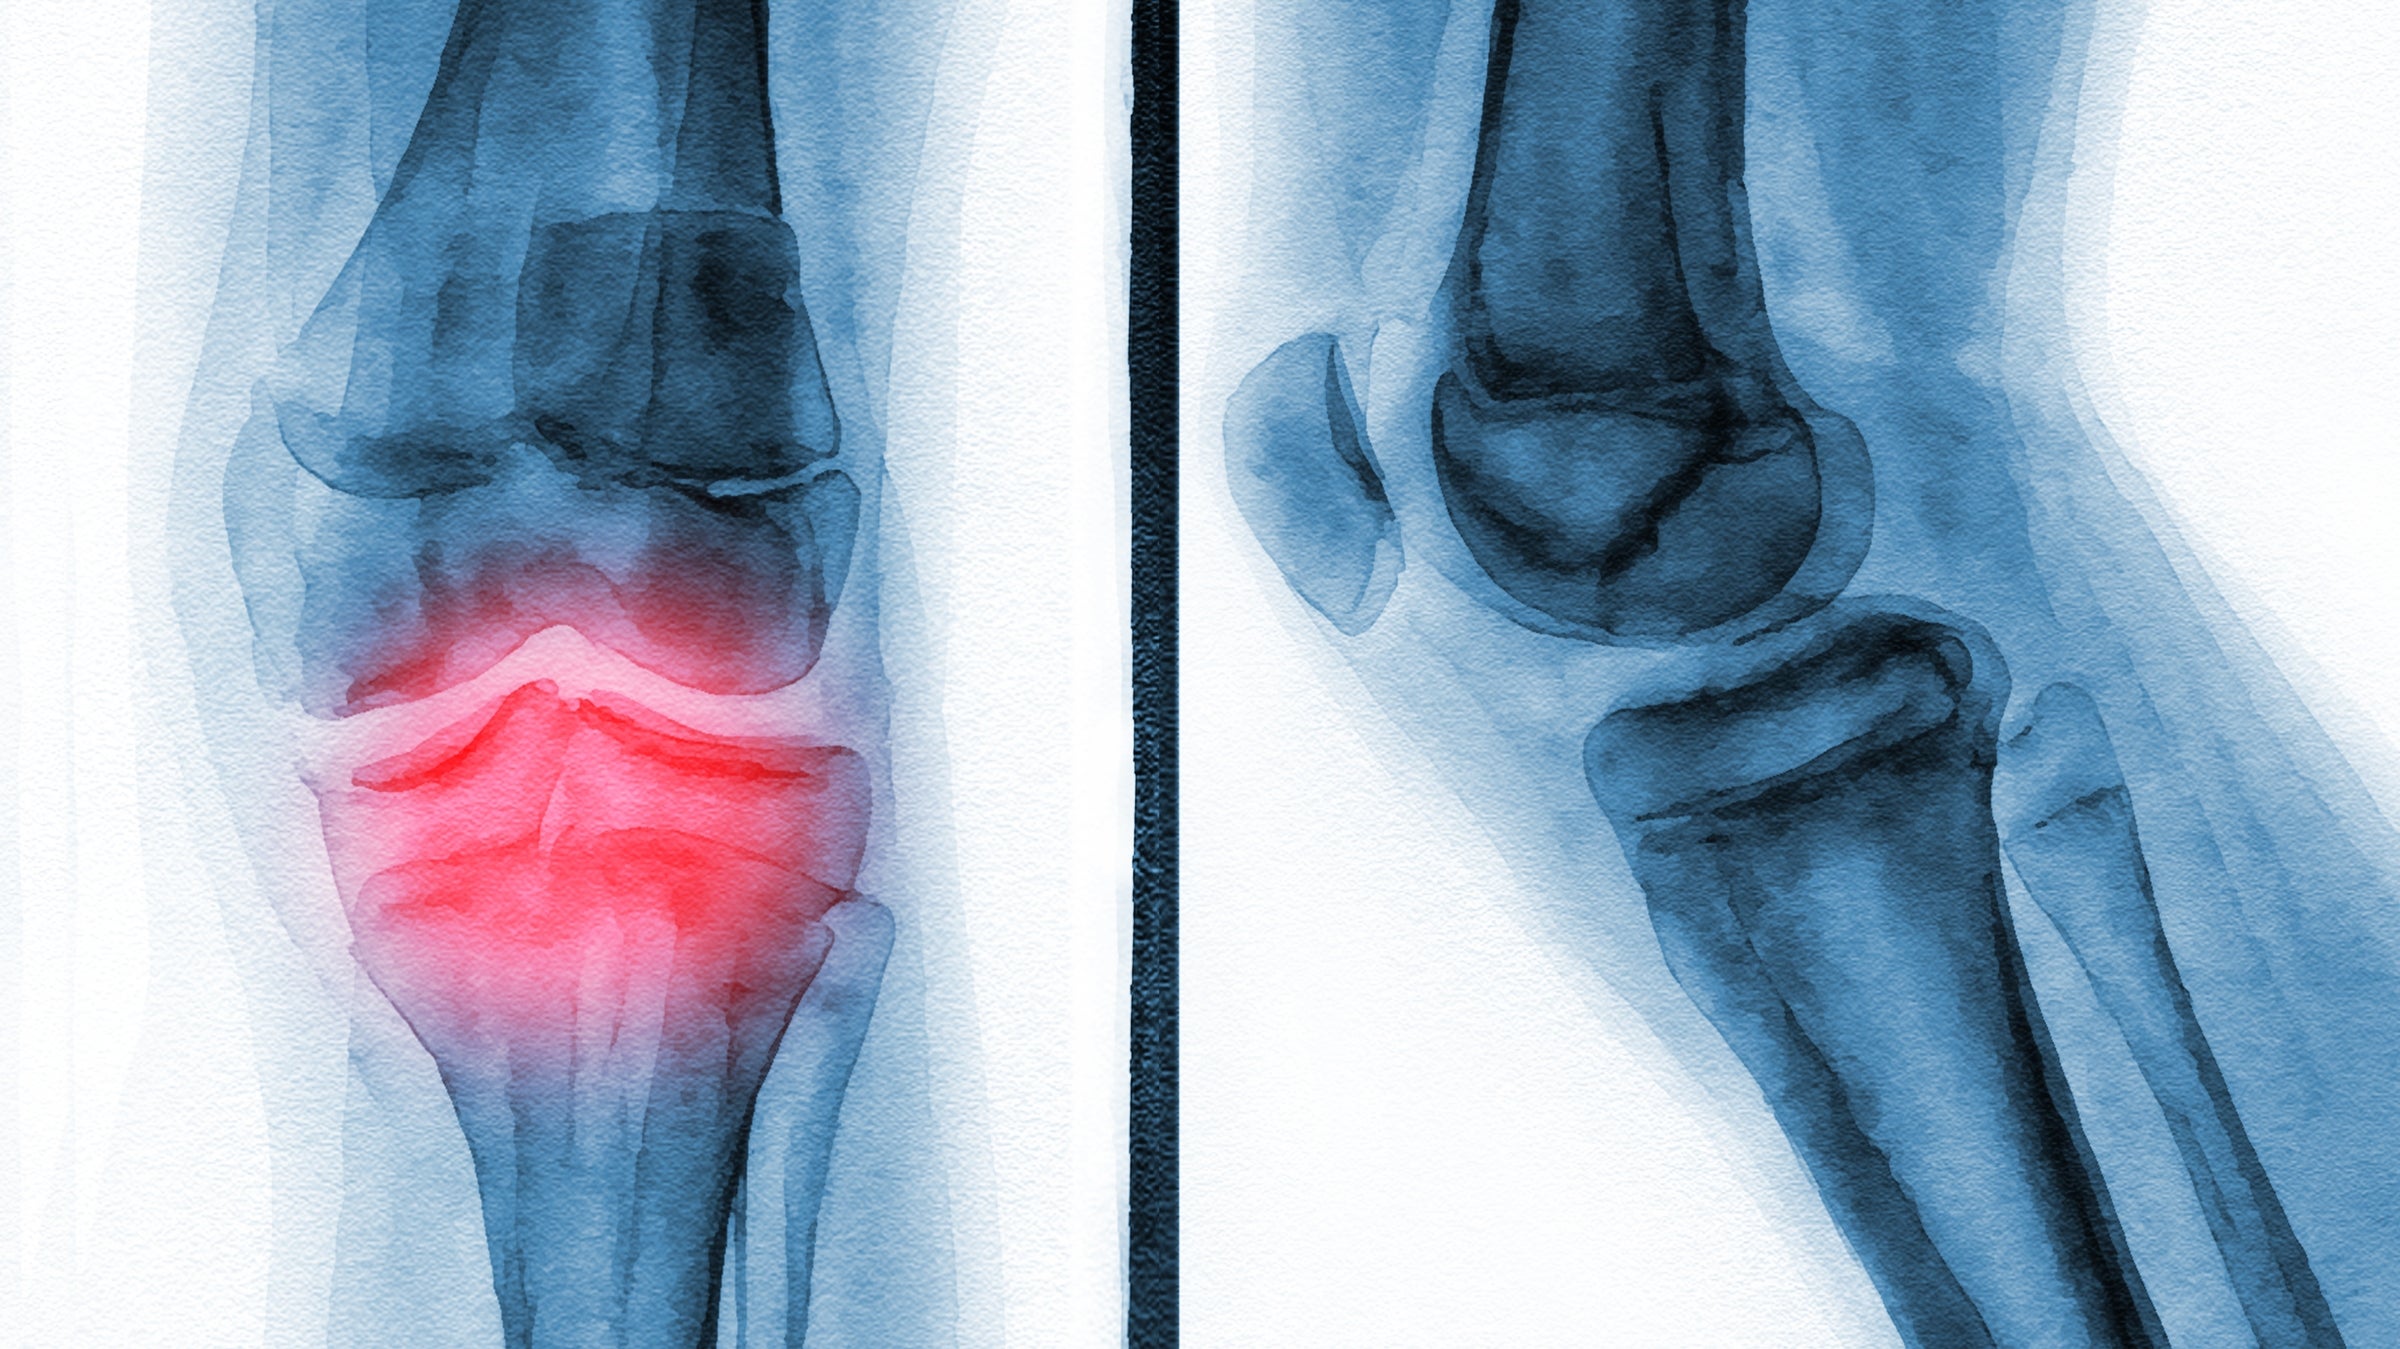

Cycling appears to be a great way to avoid arthritic knee pain. (Photo: sbk_20d pictures/Getty)

About half of the subjects reported some history of cycling, and the headline result is that these people were less likely to have osteoarthritis in their knees. Osteoarthritis, or OA for short, is when the cartilage that helps your joints move smoothly starts to break down; it’s sometimes referred to as the “wear-and-tear” version of arthritis, though we’ll come back to why that’s a misnomer. You can diagnose OA with an X-ray showing the bones on either side of the joint coming closer together, or even coming into contact with each other. But what you see in an X-ray doesn’t always correspond to what you feel. The study used three different outcomes: persistent knee pain, radiographic OA (based on the X-ray), and symptomatic OA (when you have both knee pain and radiographic OA).